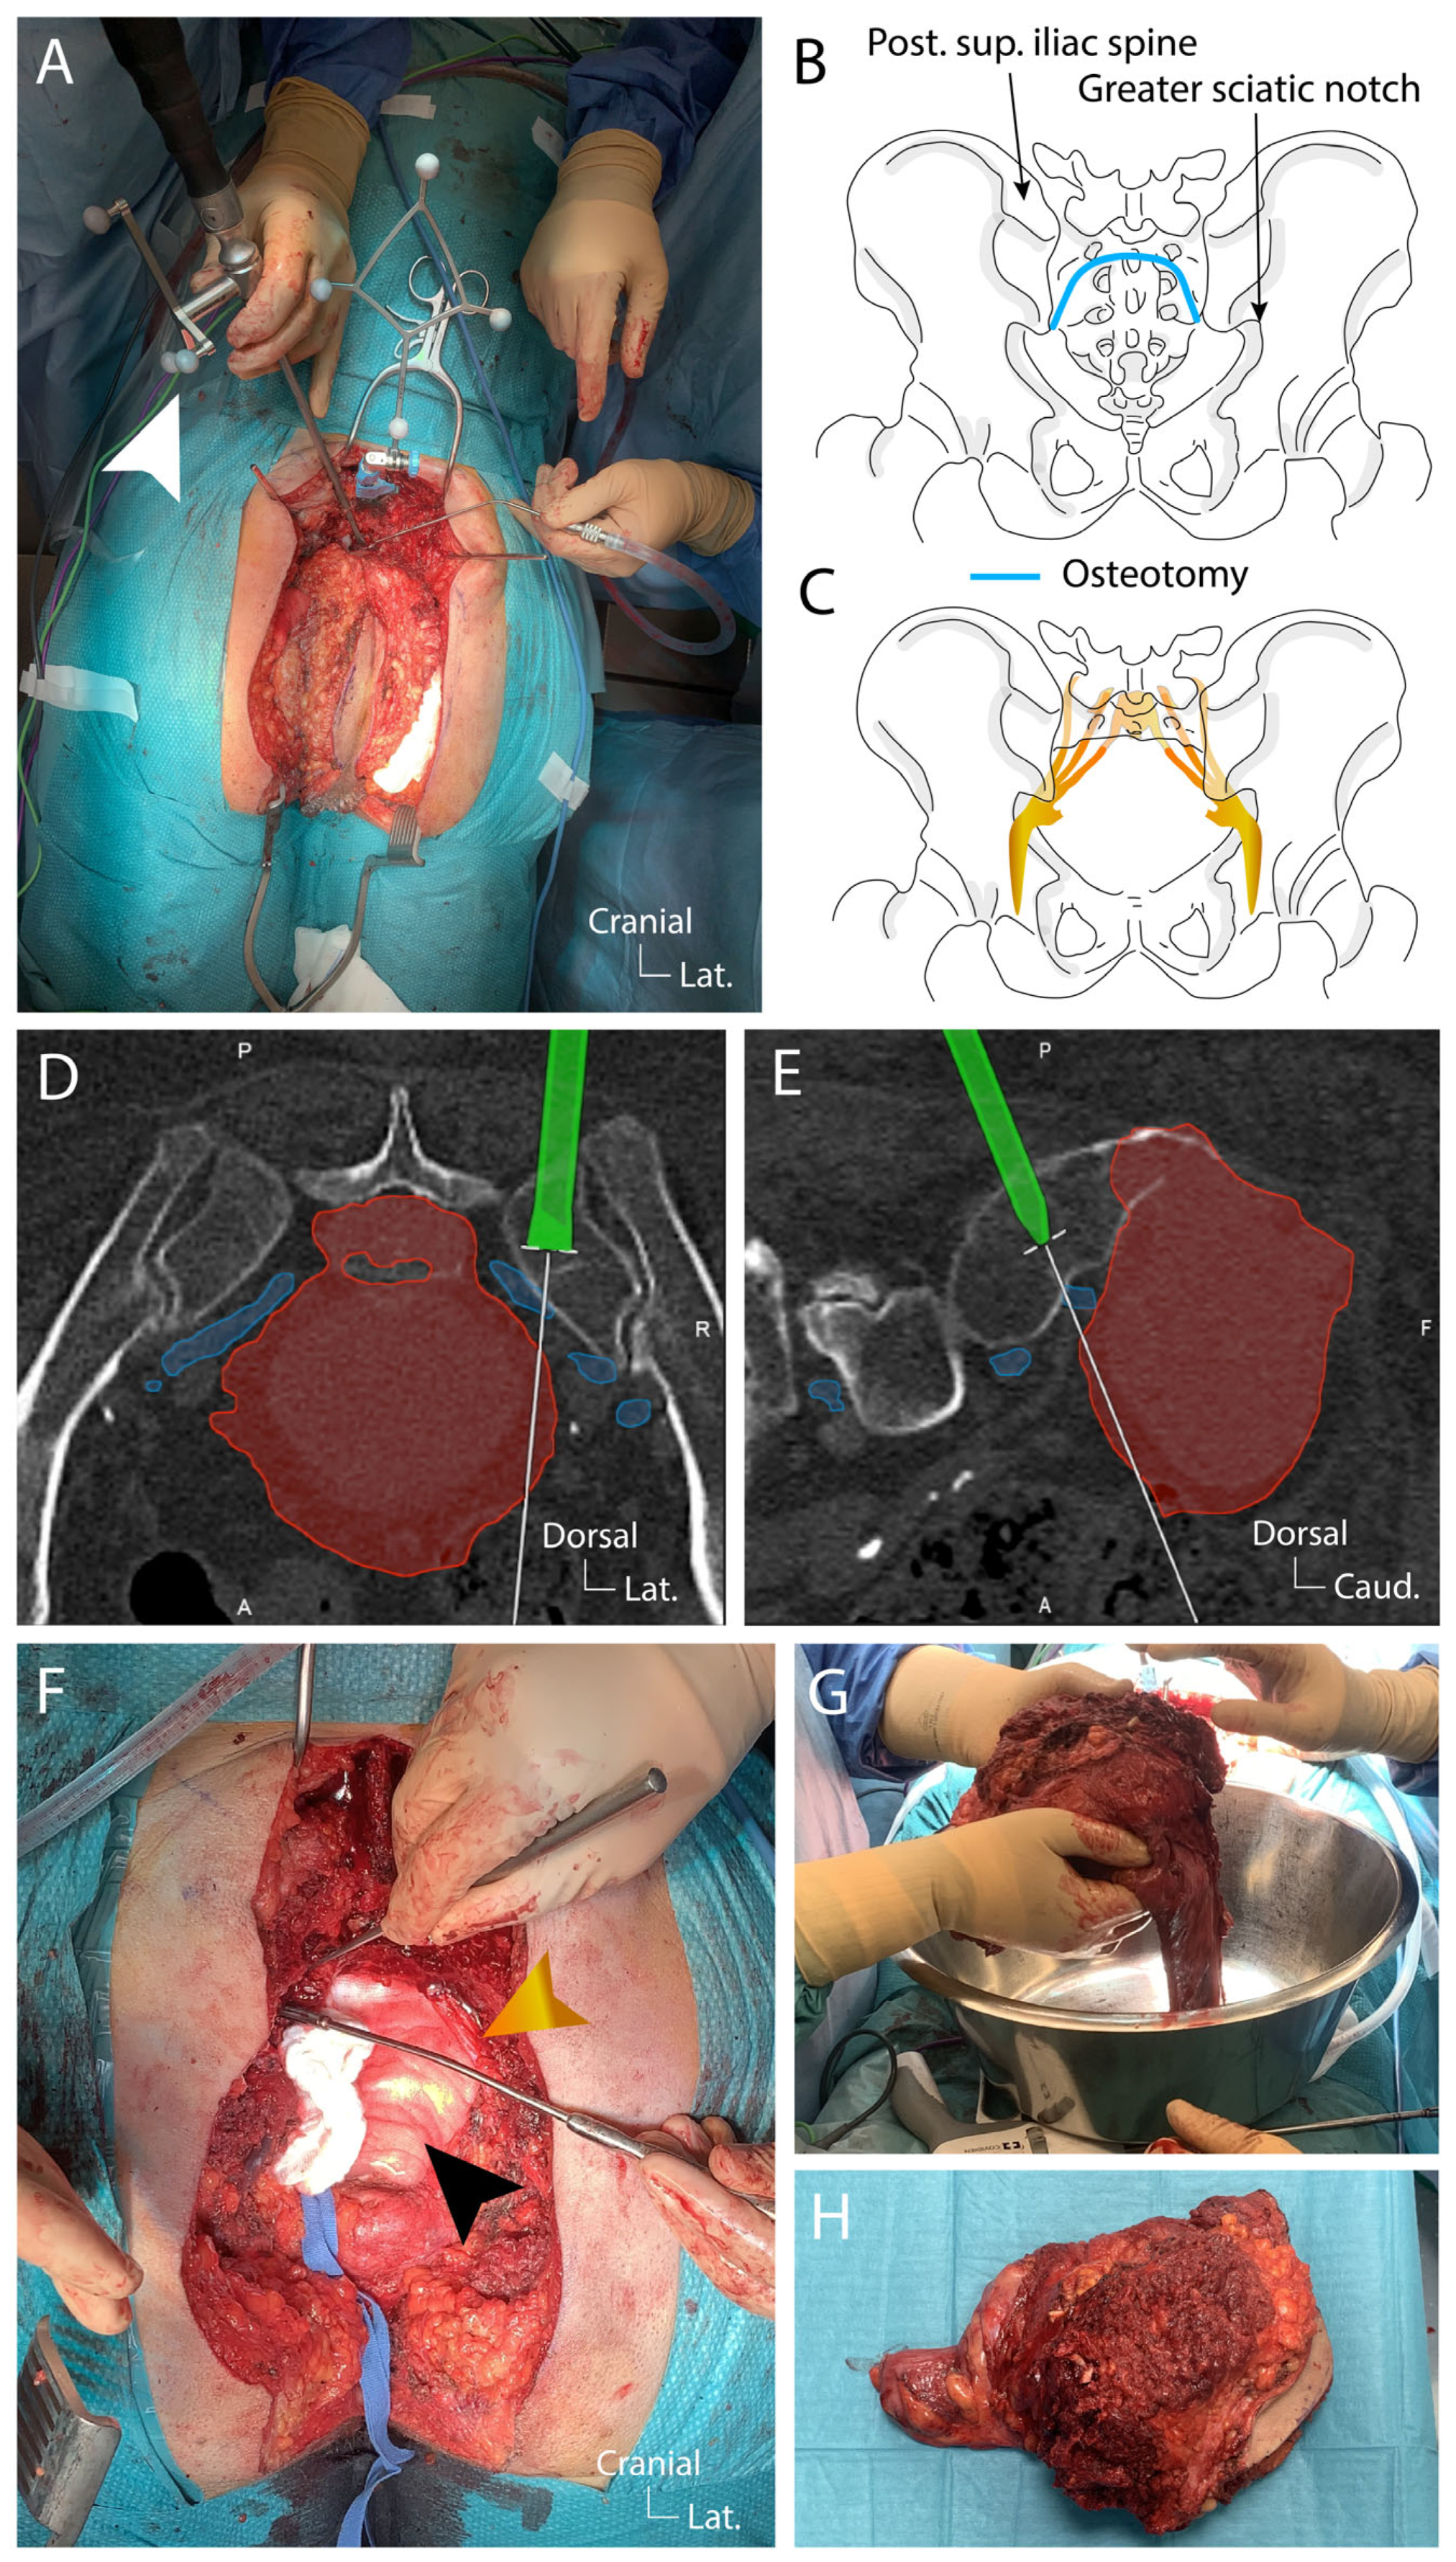

4.3. Surgical Technique